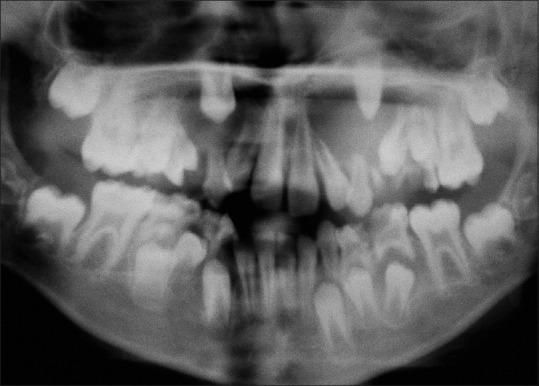

Dentigerous cysts are the most common developmental cysts of the jaws, accounting for approximately 20% of all jaw cysts. These cysts are usually unilateral, surrounding the crowns of impacted mandibular third molars. Bilateral dentigerous cysts have been associated with syndromes such as cleidocranial dysplasia and Maroteaux-Lamy syndrome. Nonsyndromic bilateral dentigerous cysts are extremely rare, particularly in the mixed dentition. Seventeen such cases have been reported till date. This article reports the eighteenth case of bilateral dentigerous cysts involving permanent maxillary canines in a 10-year-old boy.